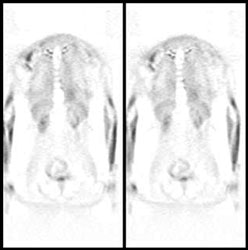

|

Intercostal muscle activity: Uptake appears to be within the ribs, but this actually represents uptake in the intercostal muscles in a patient with severe COPD. COPD patients use their intercostal muscles for breathing. |

|

|